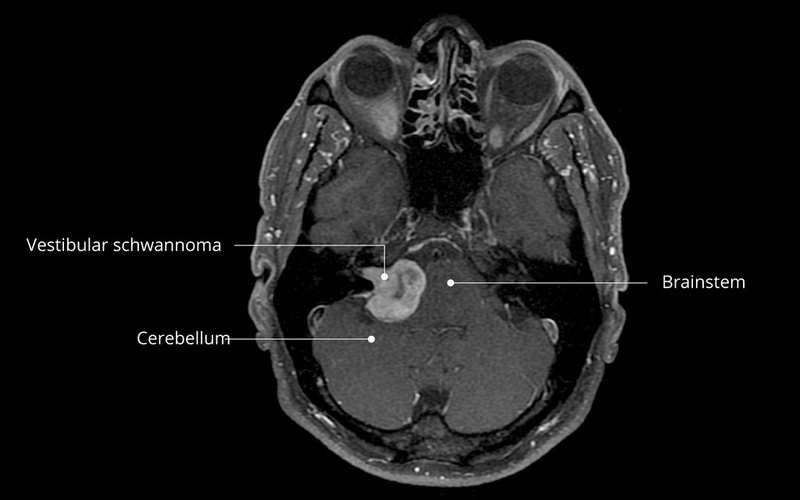

Schwannoma là những khối u hiếm gặp và chúng được phát sinh từ các tế bào schwannoma nằm trong vỏ bọc thần kinh. U schwannoma thường được tìm thấy trong hệ thống thần kinh trung ương, tủy sống hoặc hệ thống các dây thần kinh ngoại biên của cơ thể. Ngoài ra, loại u này còn được tìm thấy trong đường tiêu hoá, ổ bụng và trung thất.

Một số loại u schwannoma có thể gây dị dạng hoặc phì đại cột sống hoặc vùng xương chậu. Mặc dù u schwannoma phát triển tương đối chậm, tuy nhiên việc loại bỏ sẽ gặp khó khăn hơn nếu khối u phát triển với kích thước lớn. Trong trường hợp hiếm gặp, người mắc phải u schwannoma ở khu vực nào bộ (schwannoma tiền đình) thì có thể bị mất thăng bằng hoặc gặp phải các vấn đề về thính lực.